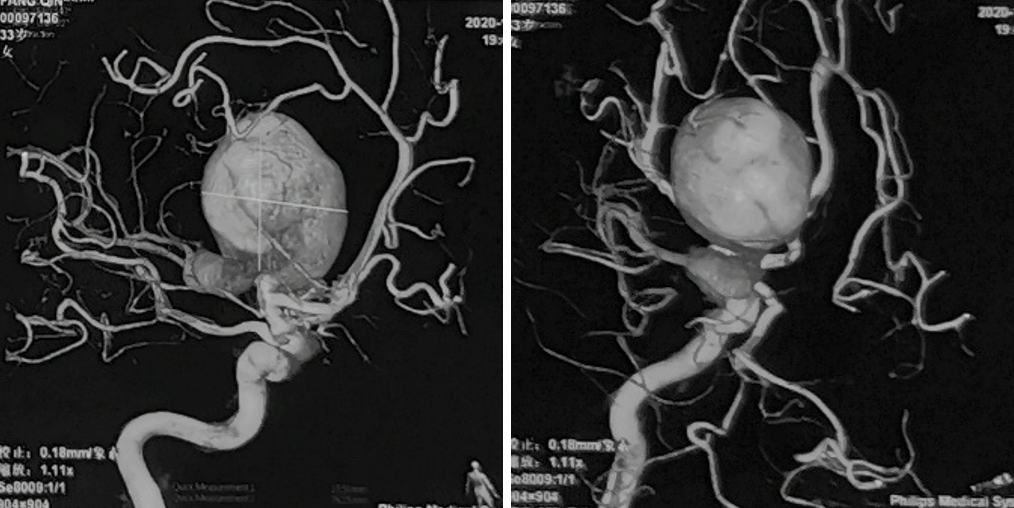

性别:女性,年龄:33 y.o

术前诊断: